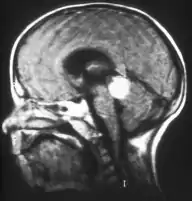

Inherited forms of retinoblastomas are more likely to be bilateral. In addition, inherited uni- or bilateral retinoblastomas may be associated with pineoblastoma and other malignant midline supratentorial primitive neuroectodermal tumors (PNETs) with a dismal outcome; retinoblastoma concurrent with a PNET is known as trilateral retinoblastoma.[15] A 2014 meta-analysis showed that 5-year survival of trilateral retinoblastoma increased from 6% before 1995 to 57% by 2014, attributed to early detection and improved chemotherapy.[16]

Aspect of trilateral retinoblastoma on MRI